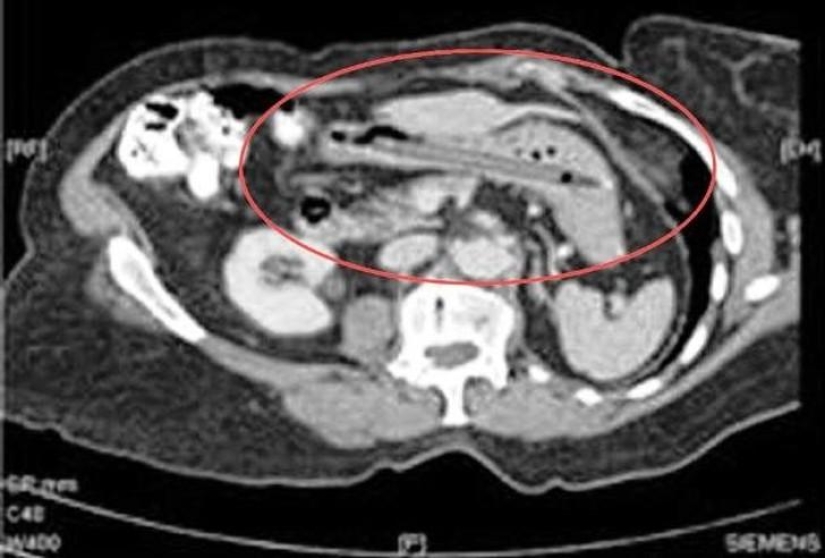

metanfetaminas